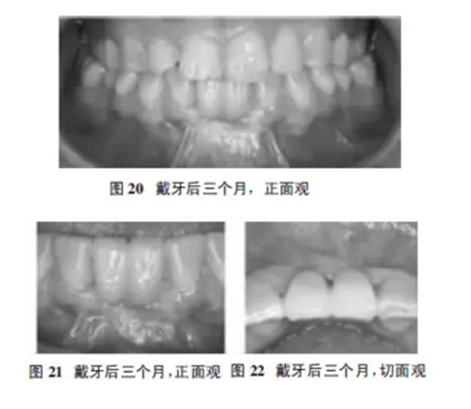

1.7戴牙后三個月復(fù)診

患者戴牙后三個月復(fù)查:患者對義齒美觀滿意,自覺無任何不適,無出血、紅腫等。CBCT示骨結(jié)合良好,植體軸向好,近遠中骨嵴穩(wěn)定。修復(fù)體穩(wěn)固無松動,叩診清音,鄰接關(guān)系好,正中及前伸無干擾,牙齦色粉、質(zhì)韌,探針無出血,無溢膿(圖20~22)。